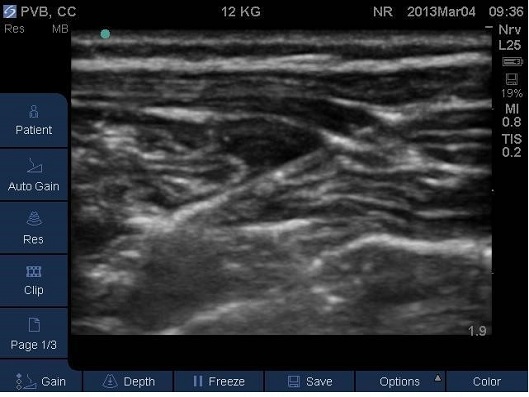

- Correct placement of the needle in the thoracic Paravertebral space should be confirmed by the anterior displacement of pleural upon injection of a small bolus of saline or local anaesthetic (Fig 13-16).

Fig 13.

Fig 14. Paravertebral space entered by needle, pleura displaced anteriorly by local anaesthetic.